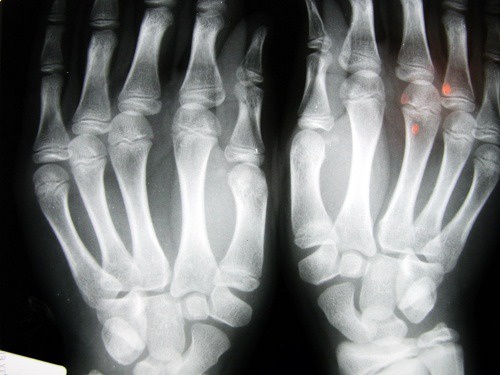

Il suono che sentiamo quando scrocchiamo le dita, i polsi, le caviglie o qualsiasi altra parte del corpo è dovuta allo scoppio di bolle contenute nel liquido che ricopre le articolazioni. Bisogna sapere che le articolazioni sono il punto di contatto tra le ossa e sono coperte da uno spesso liquido sinoviale. Quando si scrocchia, si stira o si piega un dito, l’articolazione si separa.

Si è provato ad analizzare diverse persone che erano solite scrocchiarsi le dita per sapere se le loro articolazioni erano danneggiate e se soffrivano di artrosi o artrite.

Quello che si è scoperto con questi studi è che le dita delle mani erano danneggiate.Molti avevano lesioni nei tessuti molli e meno forza nell’afferrare gli oggetti. Questo sembra essere collegato allo stirare e contrarre, rapidamente e in continuazione i legamenti delle articolazioni.

Un altro studio convolse 30 anziani di un ospizio di Los Angeles. Coloro che si erano scrocchiati le dita durante la loro vita, non soffrivano di osteoartrite. In un terzo studio, fatto su adulti di 45 anni di Detroit, si scoprì che il problema riguardava l’afferrare, che era meno forte e inoltre, in più dell’ 80% dei casi, soffrivano di gonfiore alle mani.